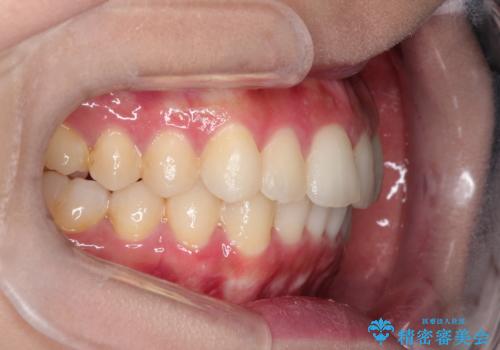

前歯のガタガタを目立たない装置でなおしたい インビザラインによる目立たない矯正

- 目立たない装置でガタガタをきれいにしたいとのご希望で来院されました。

インビザラインで矯正することとなりました。

左上の前から2番目の歯が通常とは異なる形態をしており、左右対称にすることはできませんでしたが、インビザラインで周りに気づかれることなく矯正治療をおえることができ、満足していただけました。